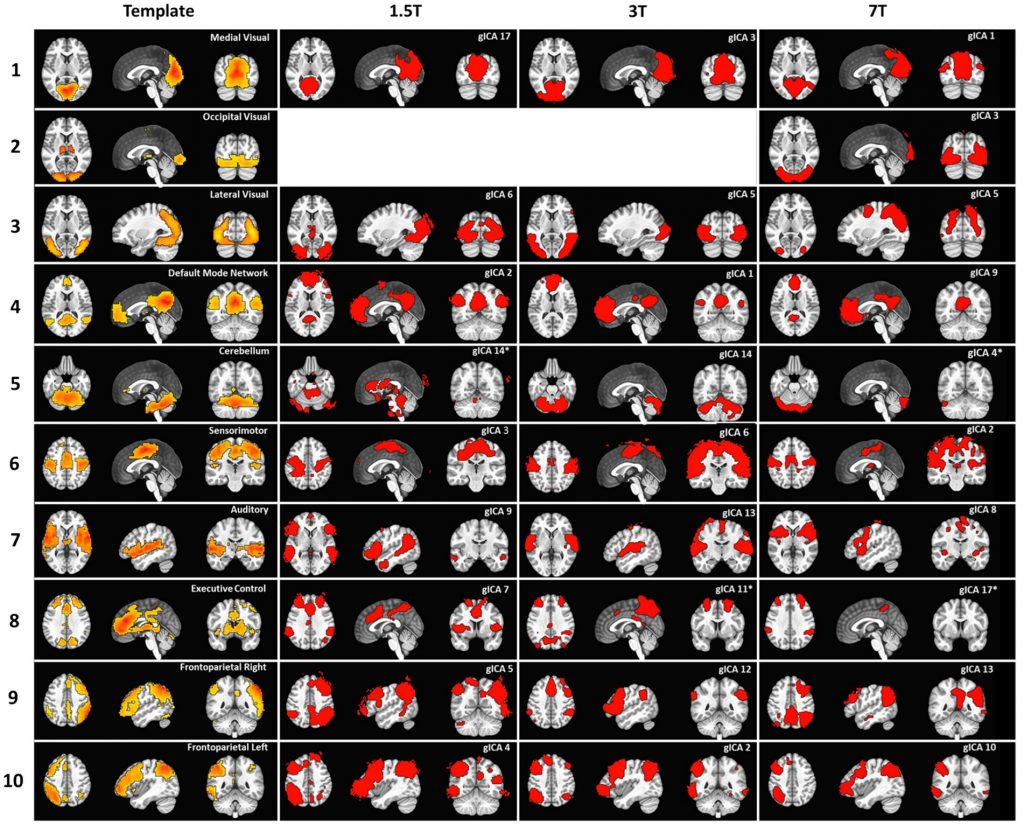

Ambrosi P, Lancione M, Cecchi P, Tosetti M, Biagi L

Robustness, spatial detail, and pitfalls of fixed ICA dimensionality in resting-state fMRI networks at 1.5, 3, and 7 T

Frontiers in Neuroscience, 19:1731143, 2025

ABSTRACT: Resting-state fMRI functional connectivity analysis is usually performed with seed-based methods that strongly rely on user-dependent definitions of regions of interest. Data-driven methods like independent component analysis (ICA) can mitigate this need. However, the number of components that should be expected in an fMRI acquisition, which determines the model order of the ICA, is not defined, and it is not uniformly chosen across studies. This variability is further complicated by the dependence of component number on field strength, with higher field strengths typically yielding more detectable components. Therefore, relying on a predetermined number may influence the results. Here, we compare functional maps obtained through ICA analysis at different magnetic field strengths and at various levels of spatial detail. Our results confirm the presence of the most frequently reported resting-state networks across field strengths and demonstrate that higher magnetic field strength enables more robust detection of functional networks with greater spatial detail. We also show that: (1) fixing the number of components, although improving interpretability of group results, may provide an incomplete picture of brain function; (2) a greater number of components is consistently identified at higher field strength, suggesting that the model order should be adapted according to both field strength and spatial detail.